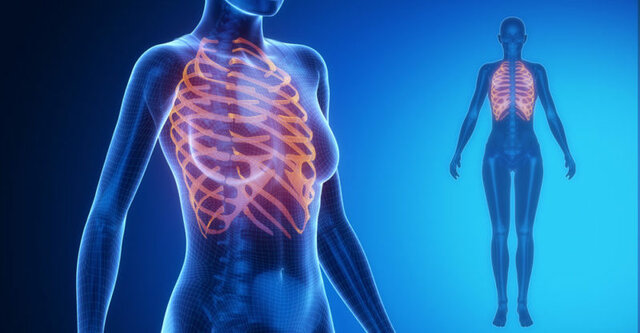

• Sarcoma de Ewing

Sarcoma de Ewing

Dr. James Ewing. Los sitios en los que este cáncer se desarrolla más comúnmente son la pelvis, la pared torácica (por ejemplo, las costillas o los omóplatos), y los huesos largos de las piernas o los brazos.